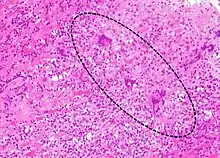

Most forms of myocarditis involve the infiltration of heart tissues by one or two types of pro-inflammatory blood cells, lymphocytes and macrophages plus two respective descendants of these cells, NK cells and macrophages. Eosinophilic myocarditis is a subtype of myocarditis in which cardiac tissue is infiltrated by another type of pro-inflammatory blood cell, the eosinophil. Eosinophilic myocarditis is further distinguished from non-eosinophilic myocarditis by having a different set of causes and recommended treatments.[34][18]

The gold standard is the biopsy of the myocardium, in general done in the setting of angiography. A small tissue sample of the endocardium and myocardium is taken and investigated. The cause of the myocarditis can be only identified by a biopsy. Endomyocardial biopsy samples are assessed for histopathology (how the tissue looks like under the microscope): myocardial interstitium may show abundant edema and inflammatory infiltrate, rich in lymphocytes and macrophages. Focal destruction of myocytes explains the myocardial pump failure.[10] In addition samples may be assessed with immunohistochemistry to determine which types of immune cells are involved in the reaction and how they are distributed. Furthermore, PCR and/or RT-PCR may be performed to identify particular viruses. Finally, further diagnostic methods like microRNA assays and gene-expression profile may be performed.